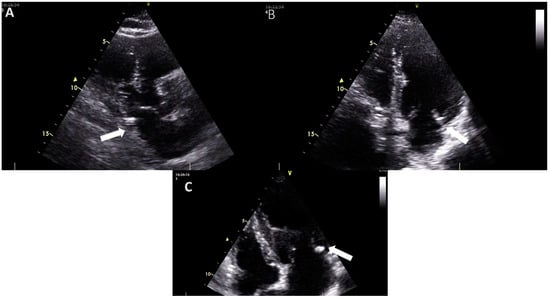

- Xu, B.; Kocyigit, D.; Wang, T.K.M.; Tan, C.D.; Rodriguez, E.R.; Pettersson, G.B.; Unai, S.; Griffin, B.P. Mitral Annular Calcification and Valvular Dysfunction: Multimodality Imaging Evaluation, Grading, and Management. Eur. Heart J. Cardiovasc. Imaging 2022, 23, e111–e122. [Google Scholar] [CrossRef]

- Nestico, P.F.; Depace, N.L.; Morganroth, J.; Kotler, M.N.; Ross, J. Mitral Annular Calcification: Clinical, Pathophysiology, and Echocardiographic Review. Am. Heart J. 1984, 107, 989–996. [Google Scholar] [CrossRef] [PubMed]

- Harpaz, D.; Auerbach, I.; Vered, Z.; Motro, M.; Tobar, A.; Rosenblatt, S. Caseous Calcification of the Mitral Annulus: A Neglected, Unrecognized Diagnosis. J. Am. Soc. Echocardiogr. 2001, 14, 825–831. [Google Scholar] [CrossRef]

- Curl, E.; Riemer, E. Caseous Calcification of the Mitral Annulus: Case Report and Brief Review. Eur. Heart J. Case Rep. 2018, 2, yty124. [Google Scholar] [CrossRef]

- Dingli, P.; Felice, H.; Mizzi, A.; Montefort, S. Caseous Mitral Annular Calcification Mimicking a Lung Tumor on Chest X-Ray. J. Family Med. Prim. Care 2017, 6, 442. [Google Scholar] [CrossRef]

- Shohat-Zabarski, R.; Paz, R.; Adler, Y.; Vaturi, M.; Jortner, R.; Sagie, A. Mitral Annulus Calcification with a Mobile Component as a Possible Source of Embolism. Am. J. Geriatr. Cardiol. 2001, 10, 196–198. [Google Scholar] [CrossRef]